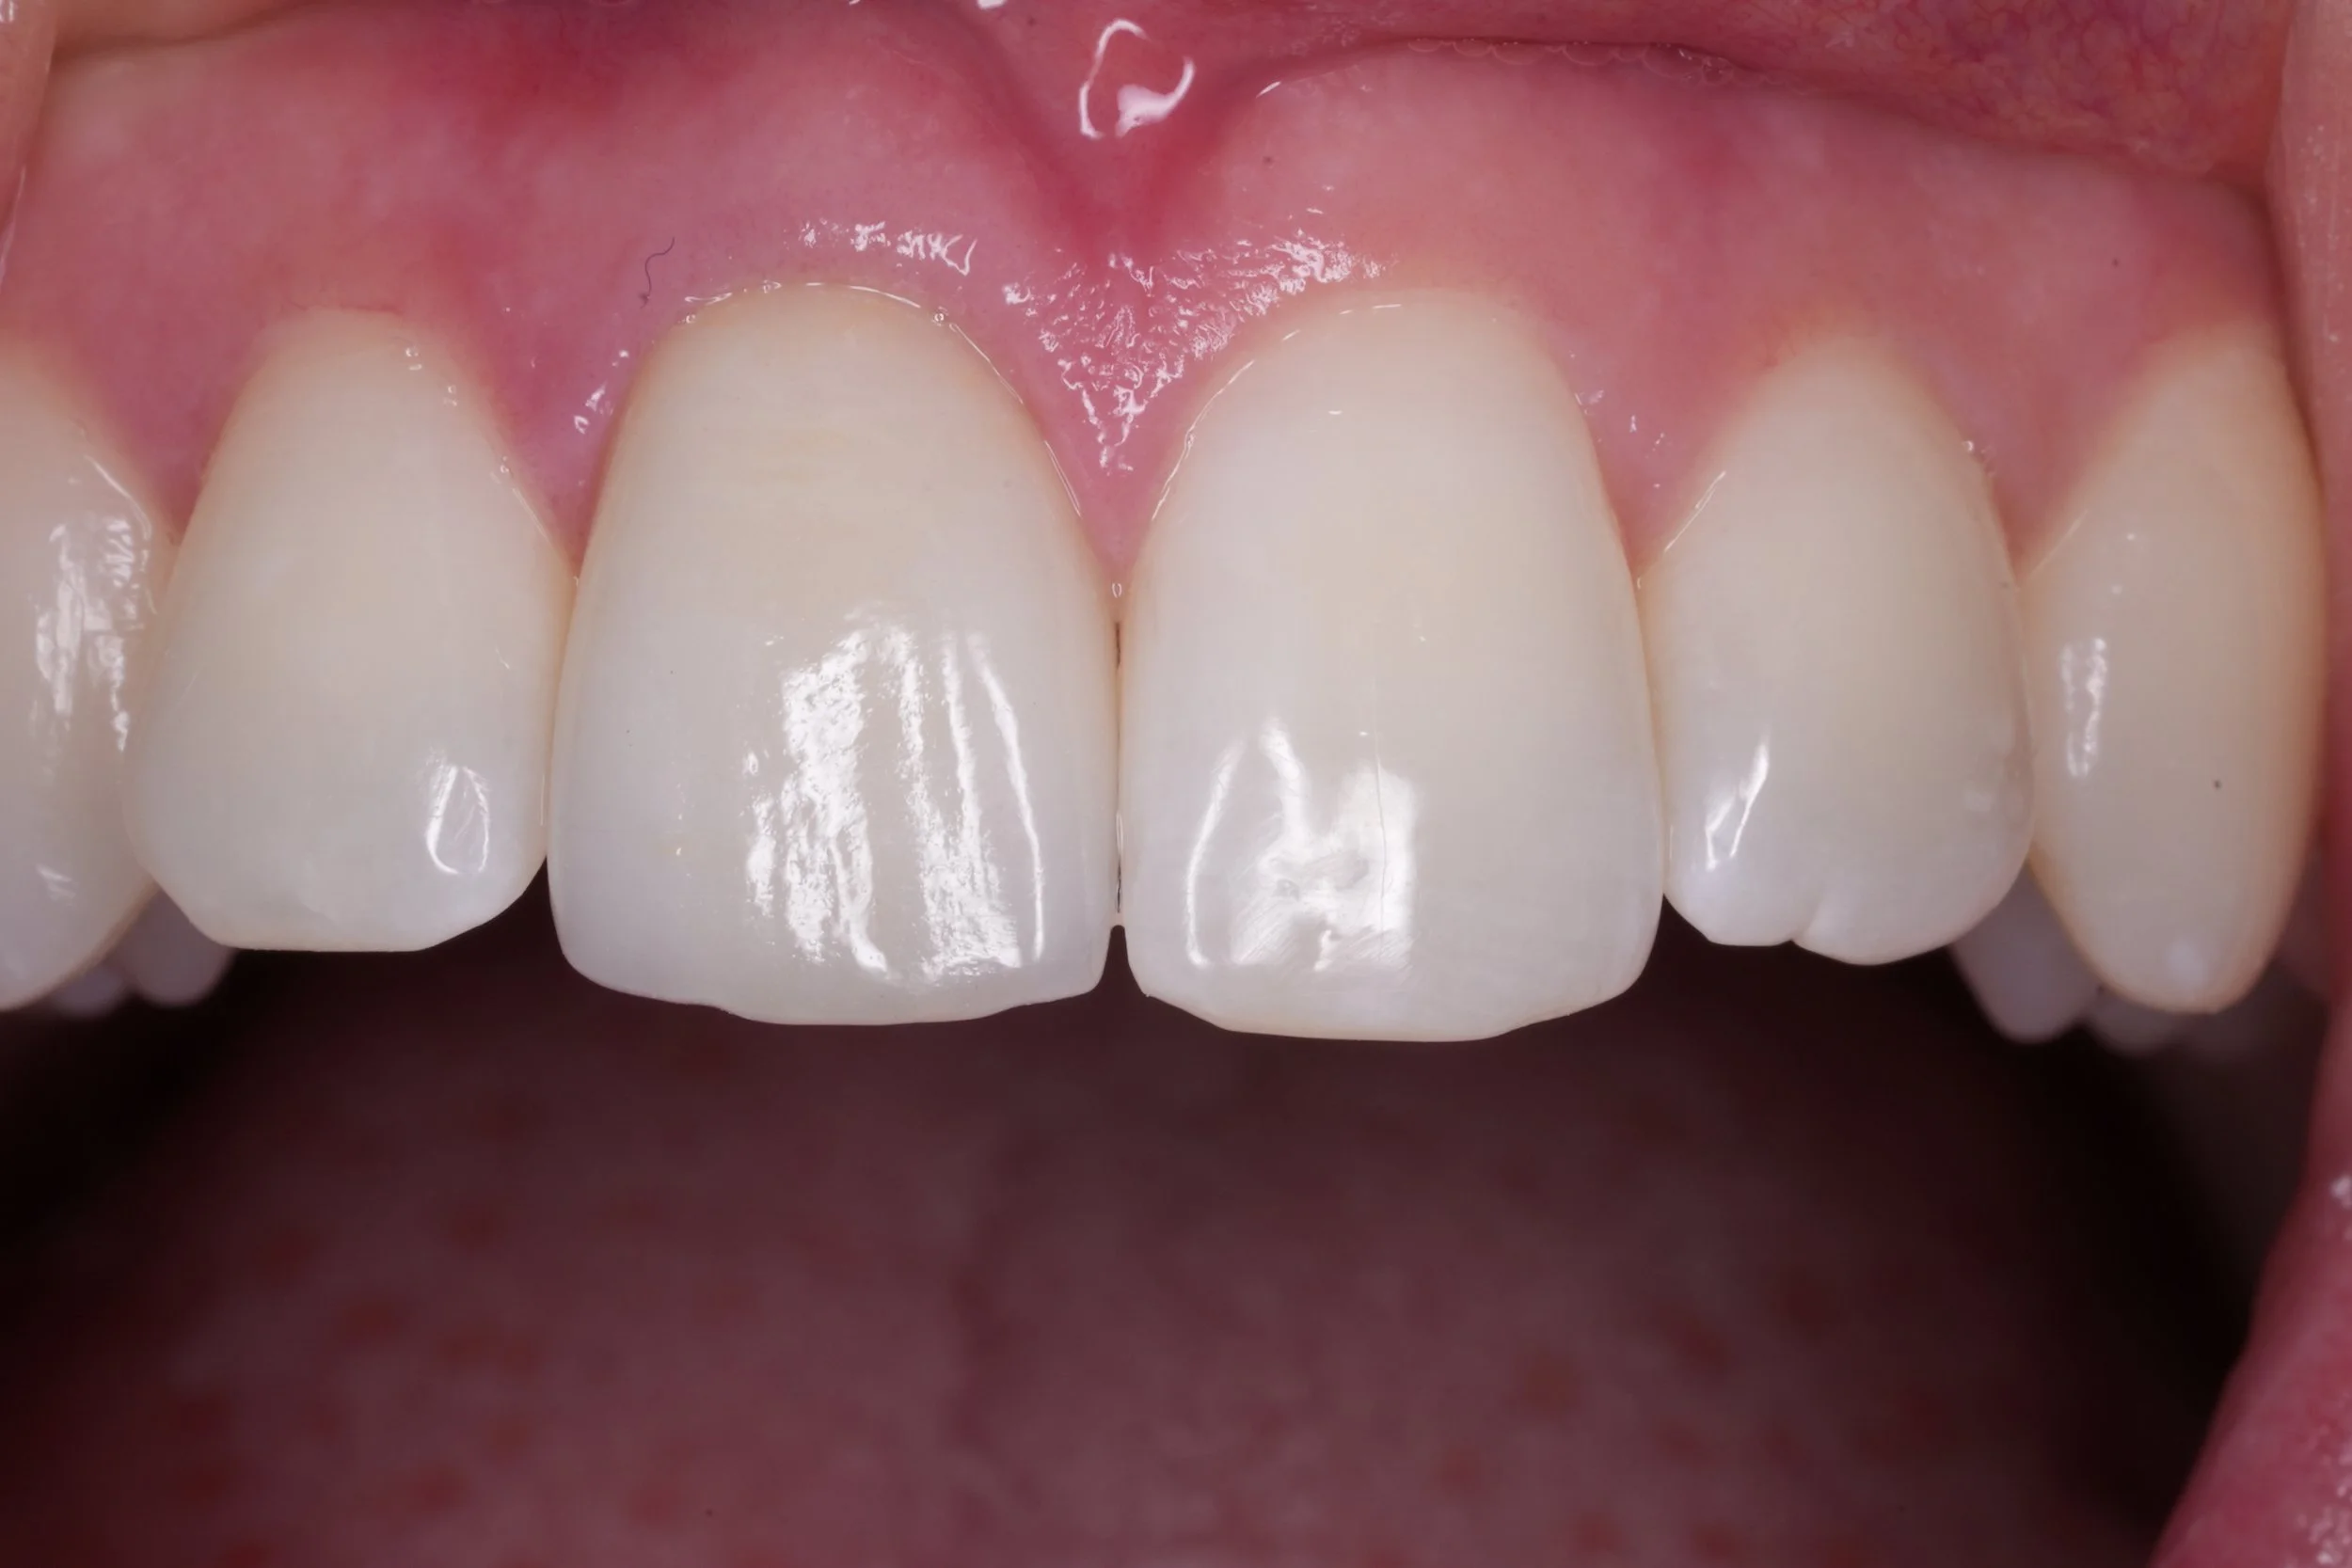

Fixed pros